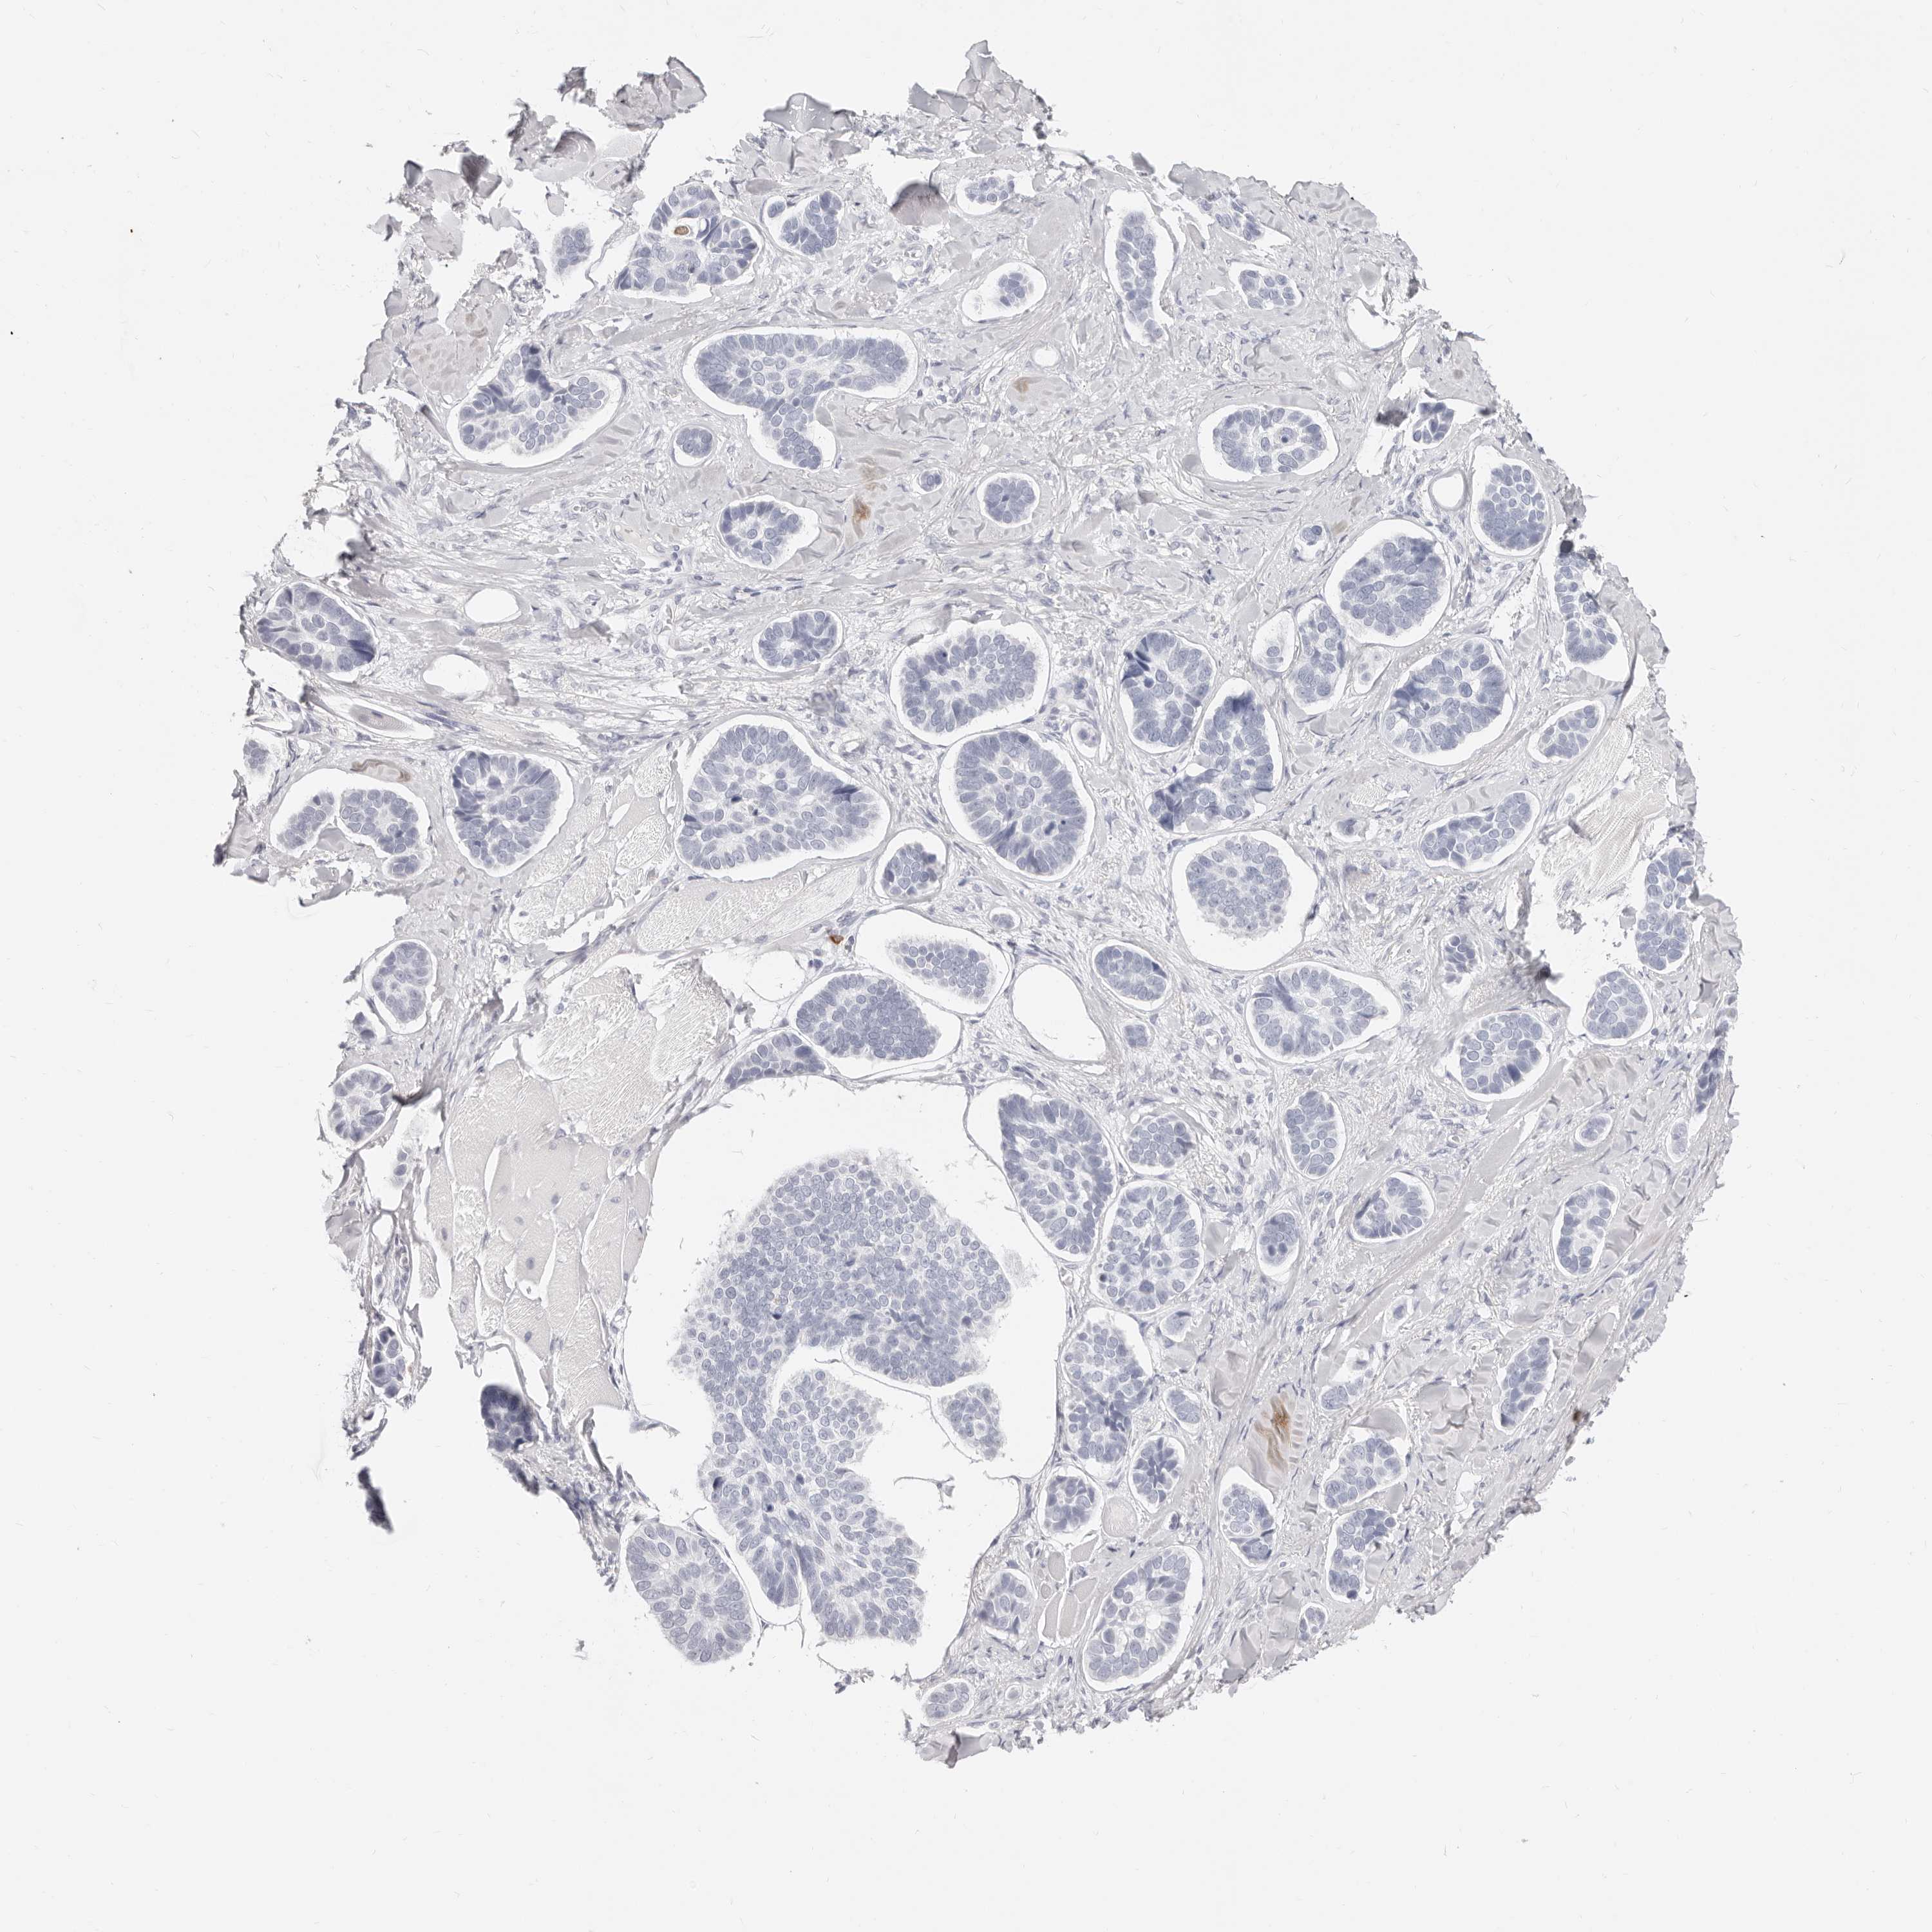

SKIN CANCER - Protein expressioni

A mouse-over function shows sample information and annotation data. Click on an image to view it in a full screen mode. Samples can be filtered based on level of antibody staining by selecting one or several of the following categories: high, medium, low and not detected. The assay and annotation is described here.

Antibody stainingi

Antibody staining in the annotated cell types in the current human tissue is reported as not detected, low, medium, or high, based on conventional immunohistochemistry profiling in selected tissues. This score is based on the combination of the staining intensity and fraction of stained cells.

Each image is clickable and will lead to virtual microscopy that enables deeper exploration of all samples and also displays staining intensity scores, fraction scores and subcellular localization as well as patient and tissue information for each sample.

Antibody HPA029874

Basal cell carcinoma